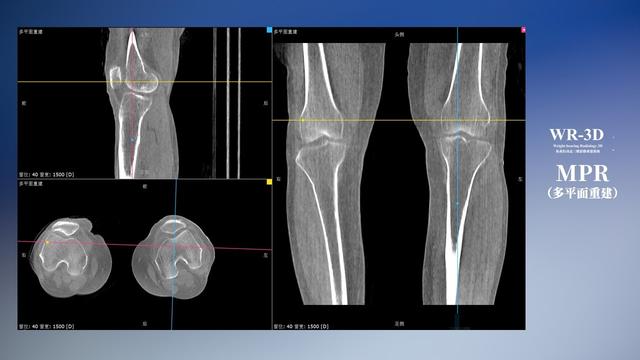

在負(fù)重位狀態(tài)下,數(shù)字化X線三維掃描與重建,能夠更好的呈現(xiàn)受檢者關(guān)節(jié)受力改變的狀態(tài)。安健科技創(chuàng)新的WR-3D動(dòng)態(tài)三維影像重建系統(tǒng),通過數(shù)字化X線攝影完成三維掃描并重建三維影像信息,包括斷層圖像重建、MPR多平面重建、MIP重建以及VR體繪制。其掃描時(shí)間短,劑量相較于CT設(shè)備大幅縮減,同時(shí)成本更低,在臨床診斷以及醫(yī)療方案制定中具有極大的價(jià)值意義。而相較于普通平片下的負(fù)重位掃描,負(fù)重位動(dòng)態(tài)三維影像重建技術(shù)能夠避免二維狀態(tài)下的組織結(jié)構(gòu)重疊、密度分辨率不足、組織解剖結(jié)構(gòu)難以分辨等問題。WR-3D支持多角度的三維觀察,能全面的呈現(xiàn)被檢查部位在多個(gè)角度下的三維影像信息,極大的降低了二維負(fù)重位檢查帶來的漏診率。

安健科技WR-3D負(fù)重位動(dòng)態(tài)三維影像重建圖像